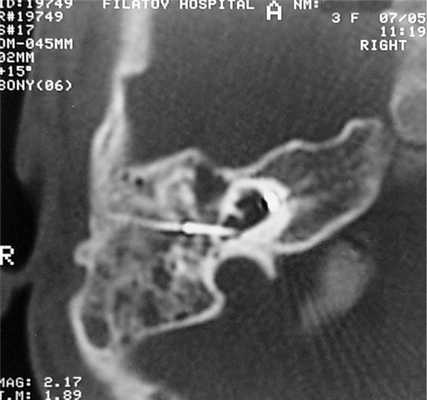

КТ височных костей выявила наличие двухсторонней аномалии развития улитки в виде неполного разделения I типа (табл. 4). При этом данное утверждение верно как для левого, так и для правого уха, несмотря на различную, на первый взгляд, картину (рис.1).

Рис. 1. Данные КТ пациентки К.

Примечание: Так, справа (1) улитка представлена небольшой полостью, максимальный размер которой составляет не более 5 мм, преддверие и полукружные каналы отсутствуют. Слева (2) улитка представлена единой полостью без внутренней архитектуры, отмечается наличие расширенного преддверия (рис. 2, стрелка); расширенная система полукружных каналов (рис. 3, стрелка).